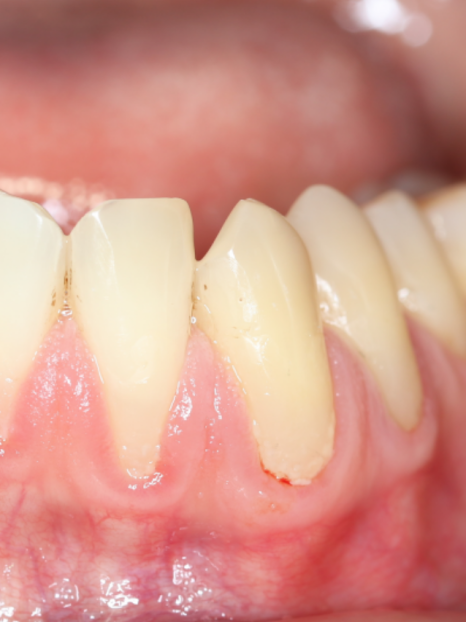

스케일링을 직접 도와드리기 위해

구강 내부를 자세히 촬영해보니

실제로 하악의 치아에 잇몸 퇴축이

발생한 것을 확인할 수 있었어요.